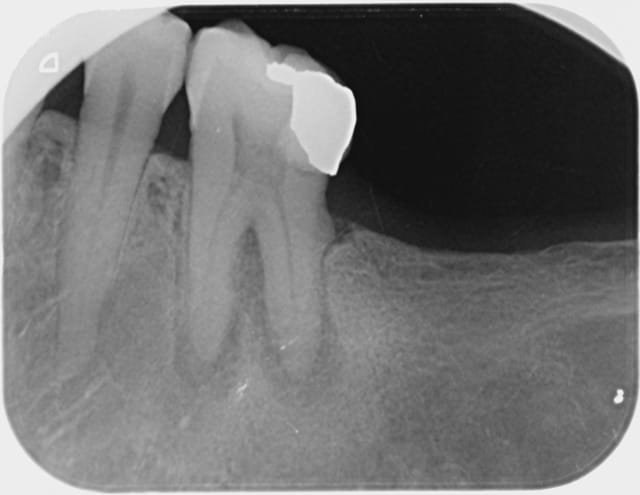

18/04/2012 à 20h03

Oulala...une endo sans digue ? Sur nonol ?

Alapex fatou 000 viafkj - Eugenol

Alapex fatou 001 hxrlfs - Eugenol

Alapex fatou 002 onq044 - Eugenol

Je vais t'aider : à supposer que tu aies fait ces radios sur une personne vivante et pas un crâne, je trouve complètement fou que tu préfères t'emmerder à faire des radios limes en place et pas mettre la digue, plutôt que mettre la digue et utiliser un localisateur d'apex qui t'évite de prendre des radios.

Maintenant, si c'est un clamp invisible, je trouve tout aussi inutile de prendre une radio, même avec la digue quand on peut utiliser un localisateur d'apex.